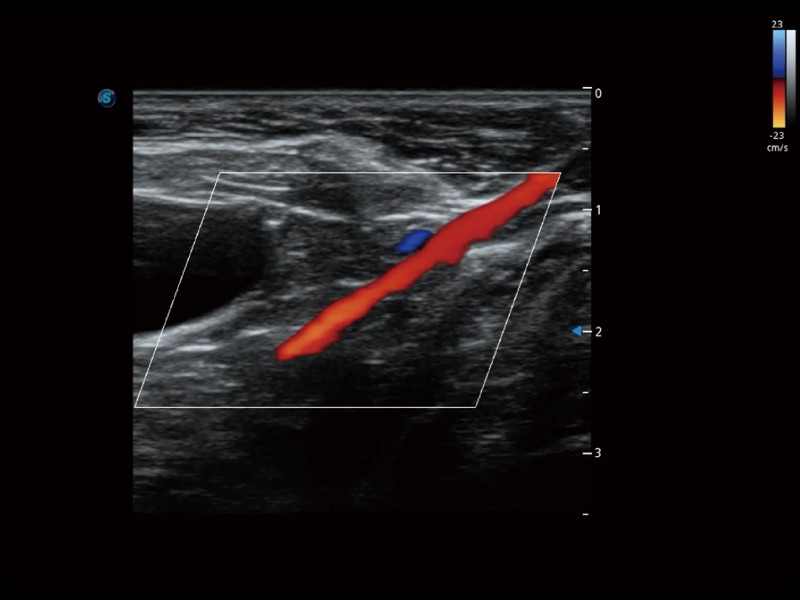

优异的基础图像

ProPet 70 全新的动物超声智能软件和丰富的探头群,为动物医生提供了高清晰度和精细分辨率的图像,无论在宠物、马科、畜牧还是实验室动物等应用中都可以轻松应对,为您的日常工作带来满意的体验。

(犬)髂动脉血流